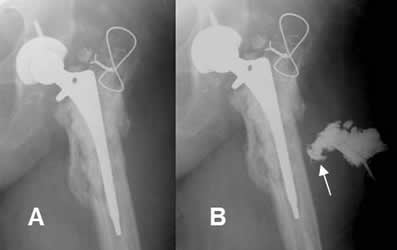

Fig 114. Aflojamiento.

A: Rx AP. Aflojamiento de la prótesis, con un espacio mayor de 2 mm. Adicionalmente hay fractura en el tercio medio del vástago. (Flecha gruesa).

B: TAC reconstrucción coronal. Aflojamiento de la prótesis.